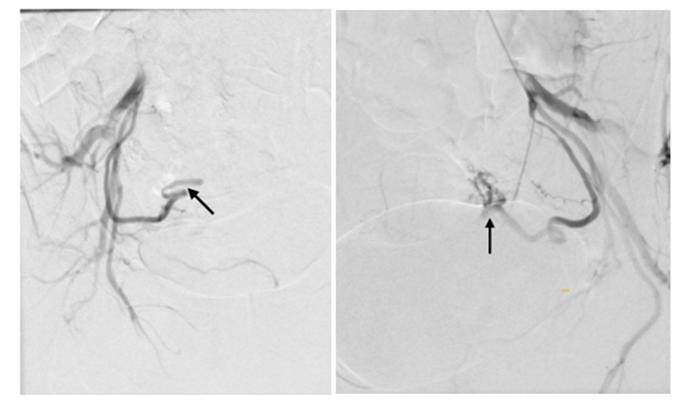

Three syringes of EMBOZENE 900 microns embolization microparticles and two syringes of EMBOZENE 1100 microns were used for embolization. A control angiography was then performed. There was prolonged (more than 10 cardiac cycles) stasis of contrasted blood in the branches of the right and left uterine, inferior vesical, and internal genital arteries supplying the pelvic organs (Figs. 5 and 6). At the final stage, a pressure bandage was applied to the puncture site of the radial artery for hemostasis. The total fluoroscopy time was 36 minutes.

Figure 5: Result of embolization of the right and left uterine arteries.

Figure 6: Result of embolization of the right and left internal genital arteries.